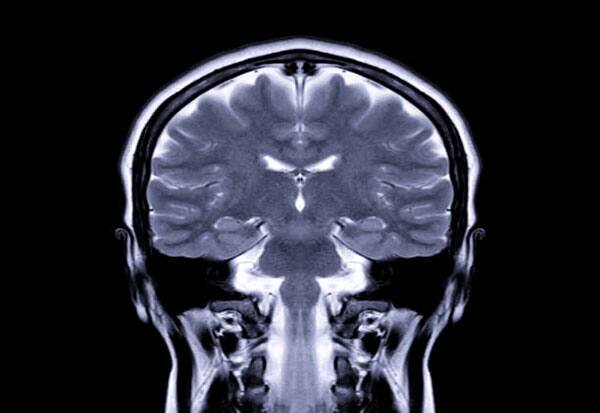

New Delhi: Denser grey matter in the cognition region of a brain could be helping serial entrepreneurs in adapting multiple strategies, enabling them to repeatedly launch new businesses compared to others, according to a recent research.

Published in the Journal of Business Venturing Insights, the research found that more grey matter in the insula in the cerebral cortex (outer layer of the brain) was linked with a higher cognitive agility by enhancing divergent thinking -- the skill of considering multiple solutions to the same problem, while not necessarily opting for the most straightforward one.

"This finding suggests that the brains of habitual entrepreneurs are specially adapted to foster the cognitive flexibility needed to identify and exploit new opportunities," said Laureys.